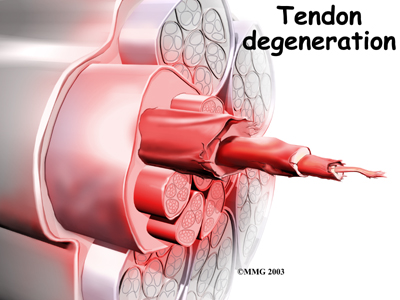

In some patients, a peroneal tendon problem is caused by degenerative changes in the tendons themselves rather than by inflammation around the tendons. The tendon itself becomes abnormal. Doctors call this condition tendonosis.

In tendonosis, the tendon becomes weakened. Tendons are made up of strands of a material called . (If you think of a tendon as a nylon rope, the collagen is the nylon strands.) in a tendon causes a loss of the normal arrangement of the collagen fibers that join together to form the tendon. Some of the individual strands of the tendon become jumbled due to the degeneration, some fibers break, and the tendon loses strength.

Over time, the tendon thickens as scar tissue tries to repair the damaged tendon. The area of tendonosis in the tendon is weaker than normal tendon. The weakened, degenerative tendon may tear. This usually causes a lengthwise in the peroneal tendons rather than a rupture. These splits or tears are most common in the peroneus brevis tendon, probably because it lies in front of the peroneus longus. It is more vulnerable to friction because it rubs against the groove in the fibula bone.